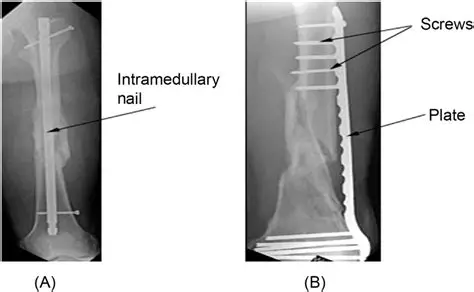

The above pictures are X-rays of a family member. This X-ray of her fracture illustrates:

internal fixation